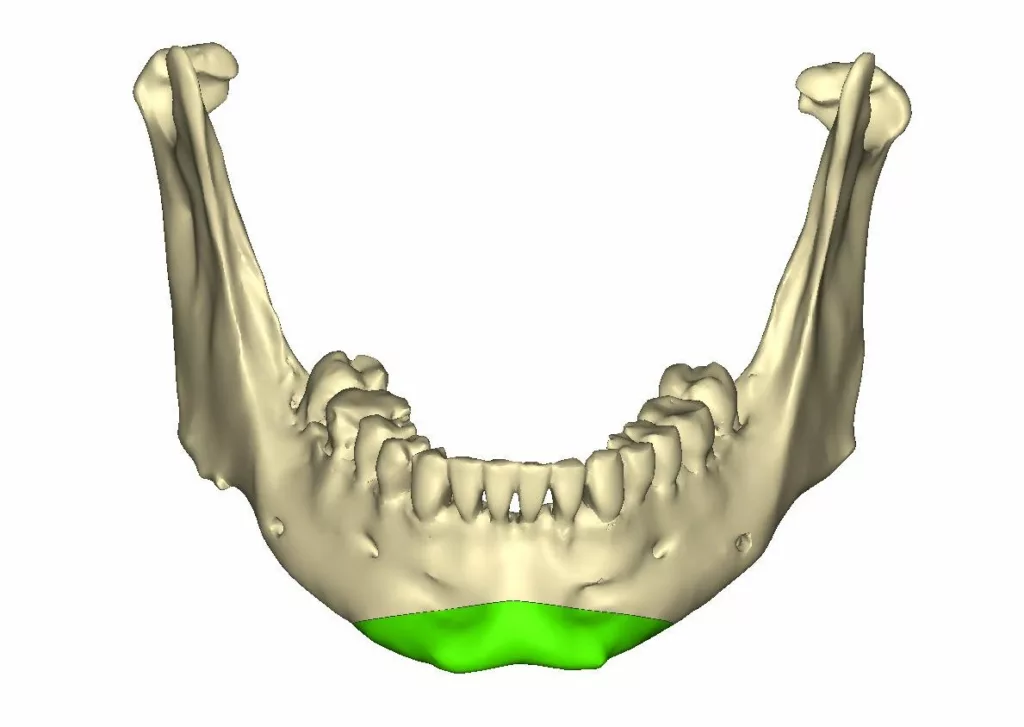

Deux types d’os coexistent au niveau des mâchoires : l’os alvéolaire et l’os basal

L’os alvéolaire

L’os alvéolaire est l’os qui entoure les dents et les maintient sur l’arcade dentaire.

L’os alvéolaire est en continuité avec l’os basal du maxillaire et de la mandibule

L’os basal

L’os basal constitue la base architecturale des mâchoires ; la mandibule en bas et le maxillaire en haut. Stable, très solide, majoritairement compact, indépendant des dents et de l’os alvéolaire, il reste présent tout au long de la vie. En cas d’édentement complet et après une longue période d’involution de l’os alvéolaire, seul subsiste l’os basal. Ce phénomène touche autant la mandibule que le maxillaire supérieur

L’ostéotomie de transposition du menton appelée aussi « Génioplastie »

Elle permet de déplacer le menton dans les trois dimensions de l’espace.

La génioplastie peut être réalisée sans ou avec une ostéotomie sagittale des branches montantes.